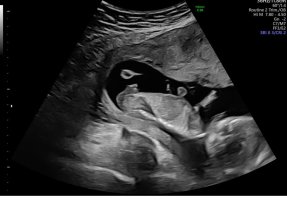

Noen som vil gjette her? 12+5. Usikker på om nub synes på disse bildene?

Jordmor tippet jente. Vi så nub mye tydeligere på skjerm. Ganske lang, rett og en liten vinkel oppover på tuppen. Da lå baby med god bøy på rygg. Andre steder så jeg den sto rett ut.

Senere sa jordmor det kunne se ut som gutt fra andre vinkler.